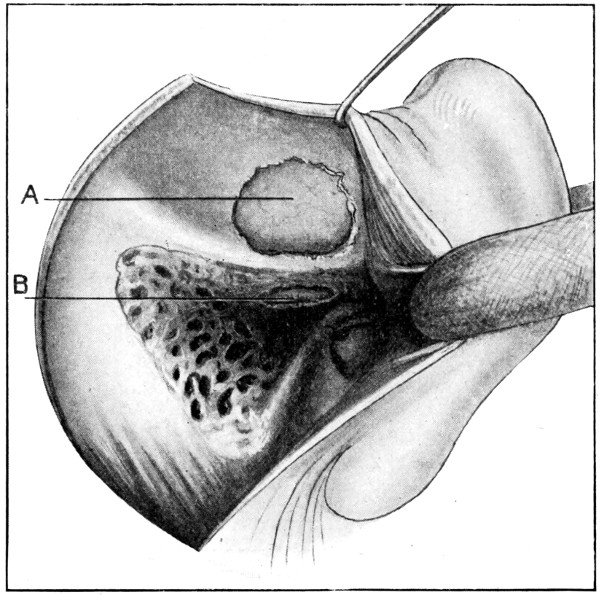

Fig. 18. Second Stage in the Formation of an Osteoplastic Flap. The bone-flap turned down and the dura mater exposed.

The dura is now separated from the bone along the line of the two vertical incisions, and the visceral blade of de Vilbiss’s forceps insinuated beneath the bone, starting at one trephine-hole and working downwards to the lower limit of the incision. It is essential that the operator should be satisfied with the ‘morcellement’ of small portions of bone at each bite of the instrument. At the lower end of each[28] of the vertical incisions the forceps is directed inwards for 1⁄4 to 1⁄2 inch so as to weaken the base of the flap.

To lift up the osteoplastic flap, a stout elevator or spatula is introduced beneath the bone at its upper part, leverage applied, and, as soon as sufficient elevation has been attained, the dura mater carefully separated from the whole of the under aspect of the flap. The flap is then grasped at its upper part with both hands and, with a quick but forcible jerk, broken across at its base, the assistant at the same time aiding the correct linear fracture of the bone by a flat spatula applied to the outer aspect of the base of the flap. Insomuch as the flap is most usually framed in the parieto-temporal region—for the exposure of the motor area—the base of the flap, being formed from the squamous portion of the temporal bone, is comparatively weak. Fracture is then readily obtained. Under other circumstances the base may be sufficiently weakened by the application of the de Vilbiss forceps or by the use of the Gigli saw.

The bone-flap is thrown back and enveloped in gauze. Its basal region is examined for a possible injury to meningeal vessels. In the event of such complications the bleeding vessel is clipped, ligatured, or underrun. Possibly some branch of the anterior division of the middle meningeal artery, running in an osseous canal, may require to be controlled by foraminal occlusion—with a wooden match, bone peg, cotton-wool, or aseptic wax.